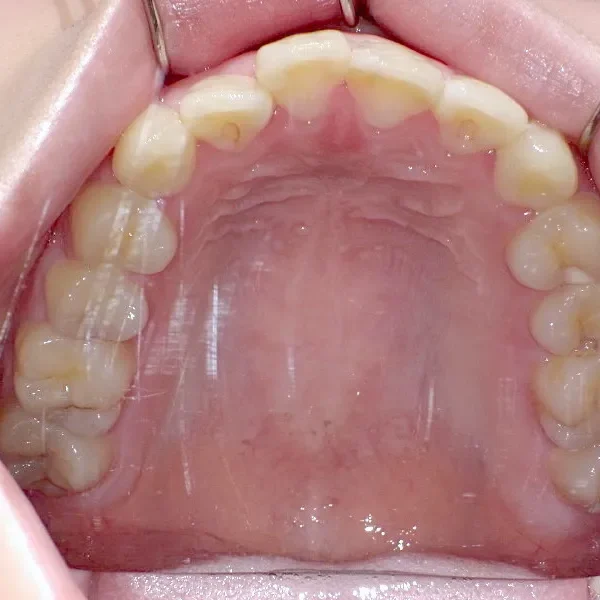

初診時年齢 19~29歳 (女性) 主訴 上下がガタガタ・出っ歯

診断名 叢生・上下顎前突 装置名

上下の歯並びがガタガタで口元が出ています。

後戻りの原因は、リテーナーの装着時間不足、頬杖や、口呼吸などが考えられます。

再治療の時は、上の歯は前から見えにくいオリジナル固定装置、下の歯はマルチブラケット装置を使用し、治療しました。

前回の治療で歯の根っこの部分の位置を治していたので、全部前から付けるのではなく最低限見える装置で治せました。